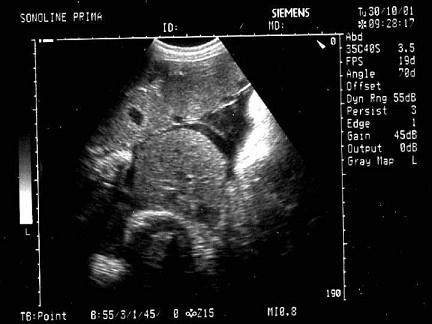

问题 女性,26岁,停经29周,产前B超检查如图,超声诊断为?(?)

选项 A.胎盘早期剥离 B.正常中期妊娠 C.胎儿脐带绕颈 D.胎儿畸形,腹壁裂 E.畸胎瘤

答案 D